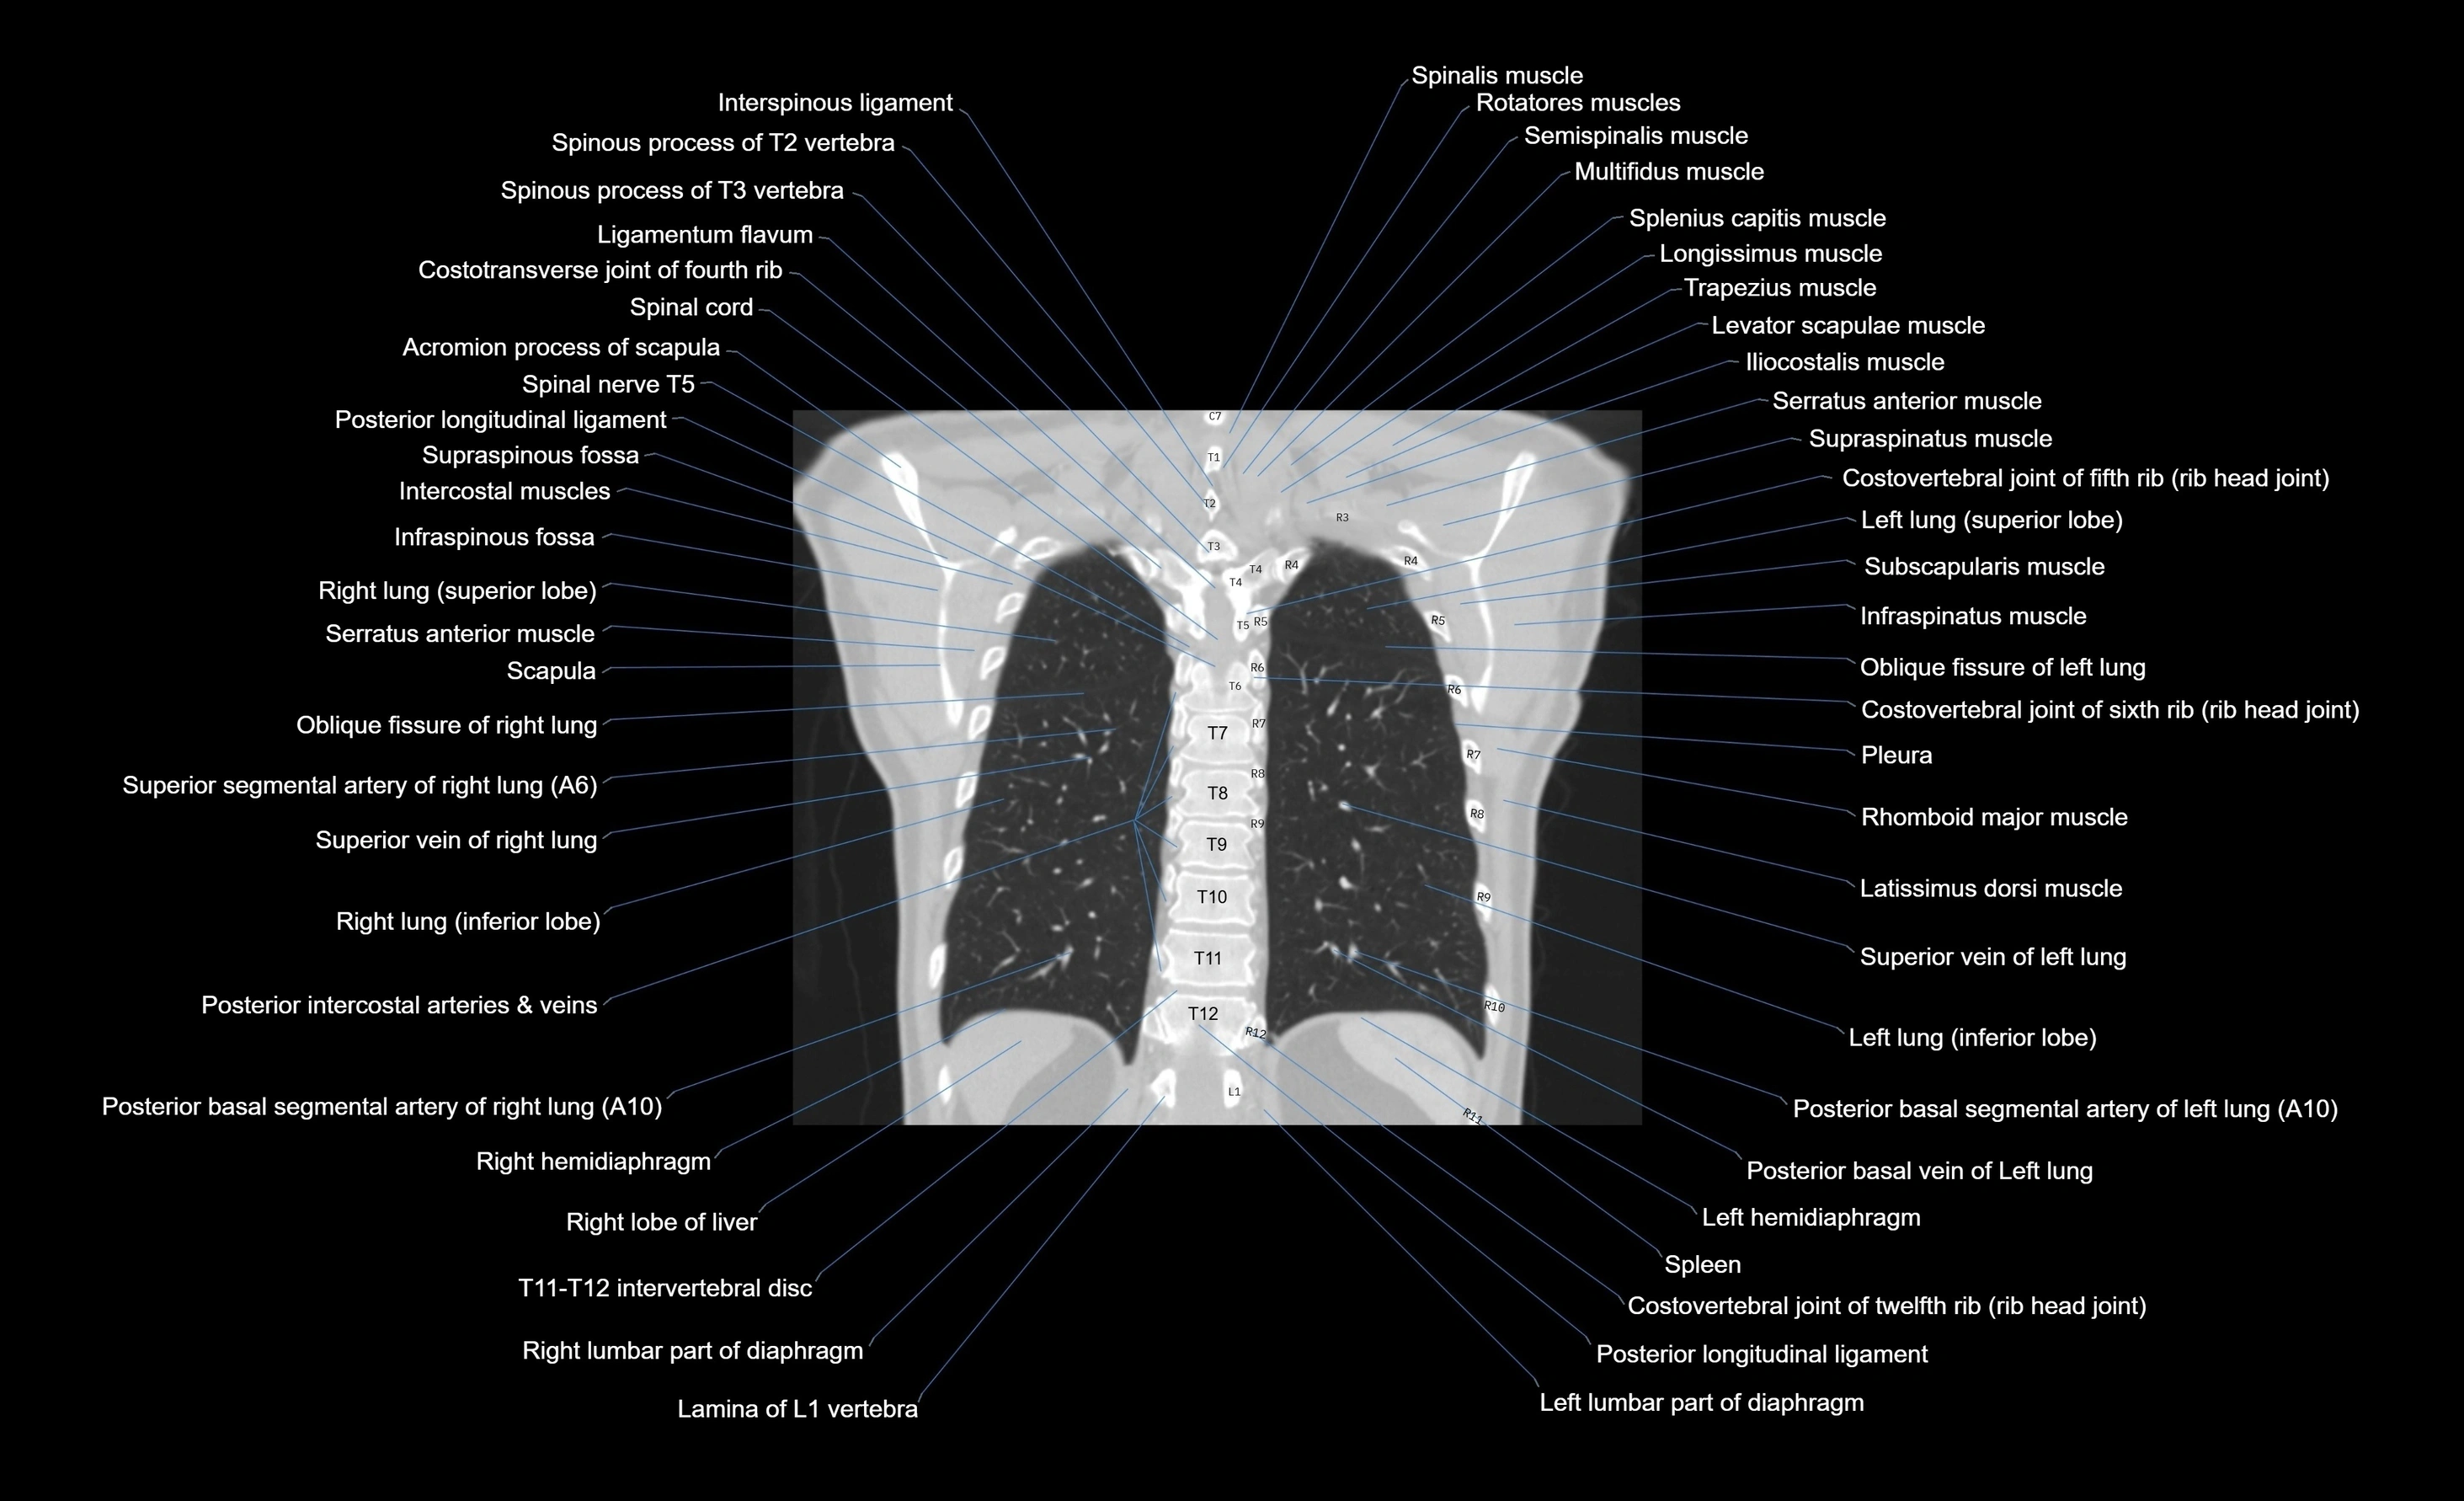

CT images